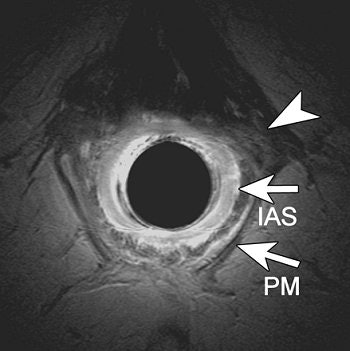

| A transverse endoanal T2- weighted fast spin-echo (2500/70) MR image (a) obtained at proximal anal canal in 69-year-old woman with complicated vaginal delivery who had undergone hysterectomy. Anal sphincters were classified as intact. Retrospectively, slight asymmetry of structures (arrowhead) located left anterolateral to the internal anal sphincter (as compared with the right anterolateral site) can be seen; these most likely represent the EAS defect diagnosed at surgery. |